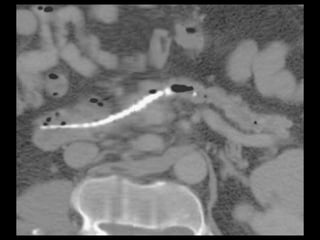

Todo o ducto pancreático pode ser visualizado num

único plano com as reformatações curvas produzidas

com os aparelhos de TCMD.